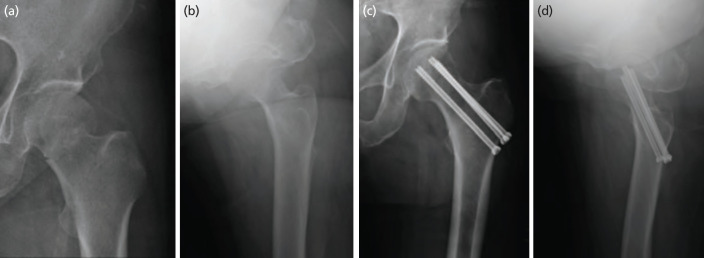

Material and methods: Among elderly patients with Garden type 1 and 2 FNFs treated between January 2010 and May 2018, 44 who were followed-up for more than 1 year were included. There were 28 cases in the CTS group and 16 cases in the CMN group, and the average age at the time of surgery was 76.3 years (range, 65-88 years). Radiological and functional variables were analysed to compare the results by fixation device.

Results: There were no significant differences between the groups in terms of functional outcomes or bone union times. However, operation and fluoroscopy times were significantly shorter in the CMN group. The neck shaft varus angulation and the extent of device sliding were greater in the CTS group. Multivariate analysis showed that CTS use was independently associated with major complications.

Conclusion: The CMN is a useful tool for treating stable FNFs in the elderly. It is simpler to use than conventional CTS fixation and is associated with fewer complications.